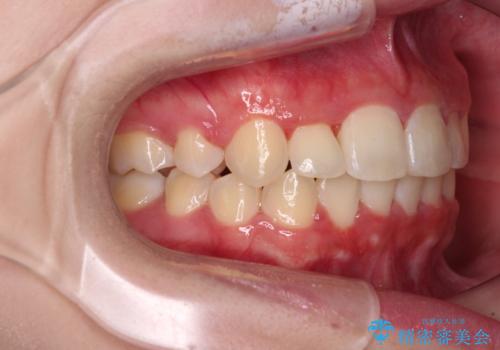

- 八重歯やデコボコをインビザラインで治療したいとのことで来院された患者様です。

インビザライン単体で治療を行うには叢生が強いと判断されたため、事前にワイヤー装置で抜歯矯正を行い、ある程度改善してからインビザラインにて仕上げていくこととしました。